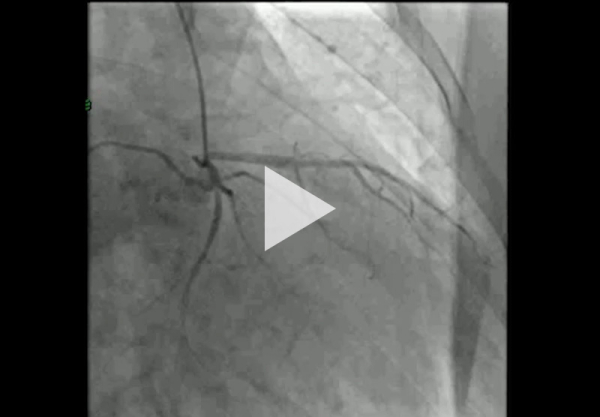

Nous optons ensuite pour une coronarographie devant sa symptomatologie de dyspnée, ses facteurs de risque cardiovasculaires et la présence d’hypokinésie du VG, en faveur d’une lésion monotronculaire avec sténose significative de la première marginale, laissée au traitement médical.

Boucles de coronarographie jointes :

- Réseau coronaire gauche (Vidéo 6)

- Réseau coronaire droit (Vidéo 7)

Vidéo 6 - Réseau coronaire gauche

Vidéo 7 - Réseau coronaire droit